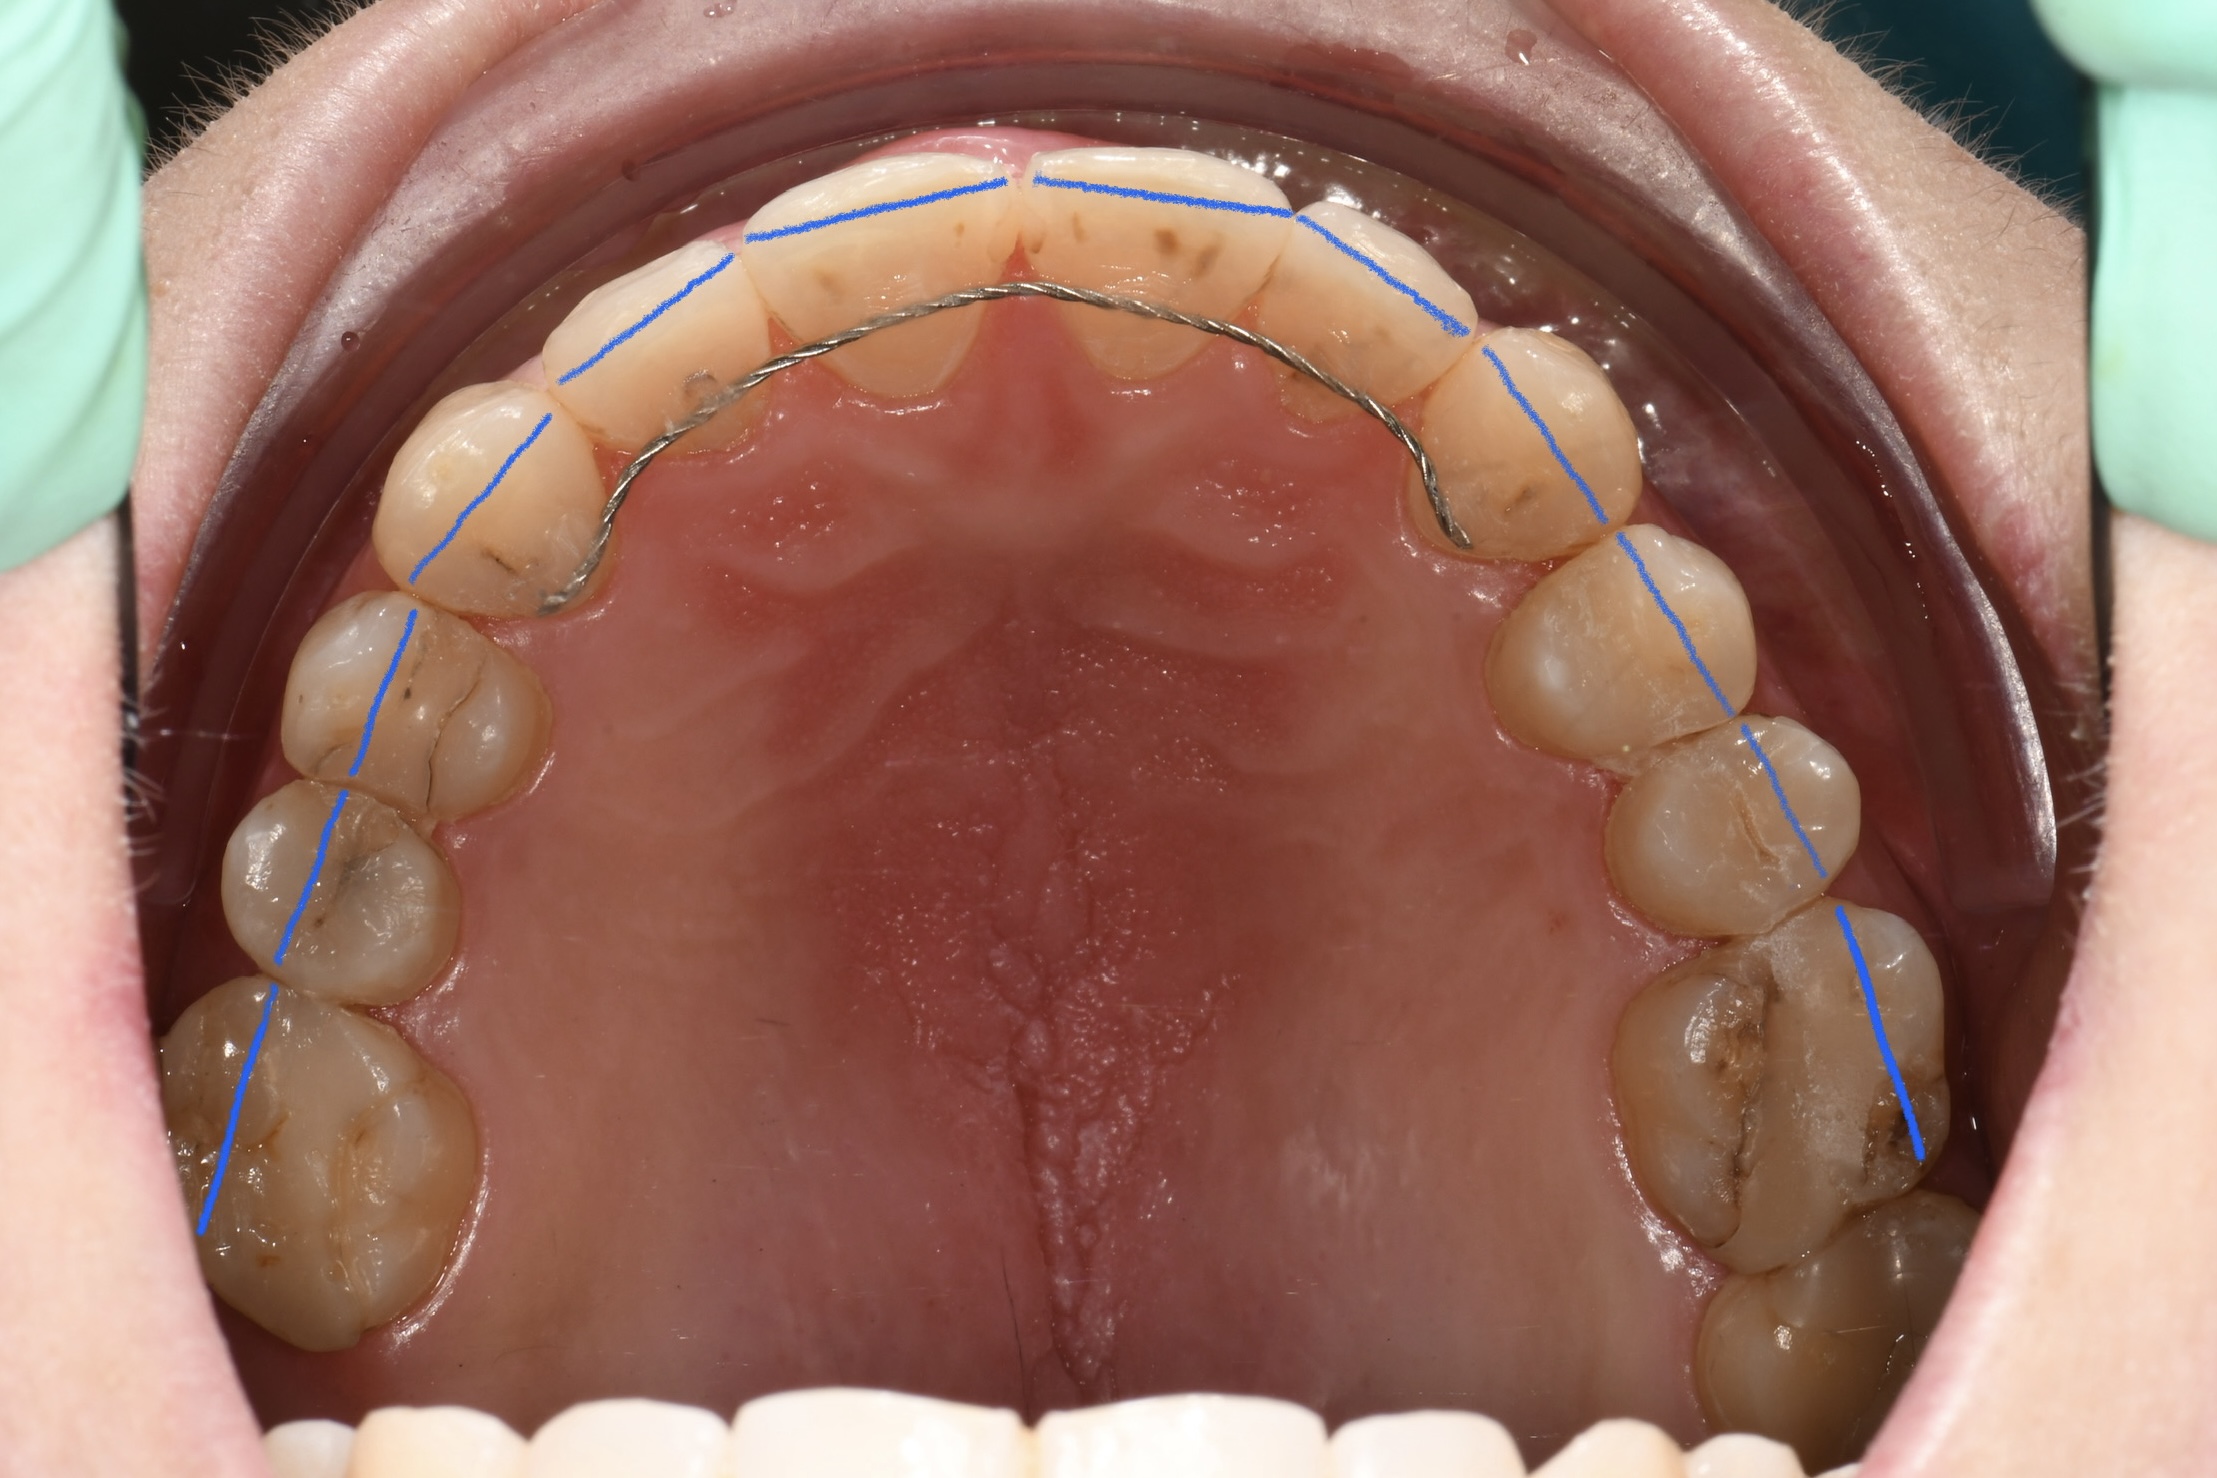

Az elmúlt évekből rengeteg szakmai referenciát tudnánk bemutatni, amelyek különböző fogszabályozási problémákat oldottak meg. Válogatva a több száz esetből, ezen az oldalon olyan képeket, információkat igyekeztünk bemutatni, amelyeknek a segítségével a jövőbeni pácienseinknek azt tudjuk üzenni: A Te fogsorod is lehet gyönyörű!